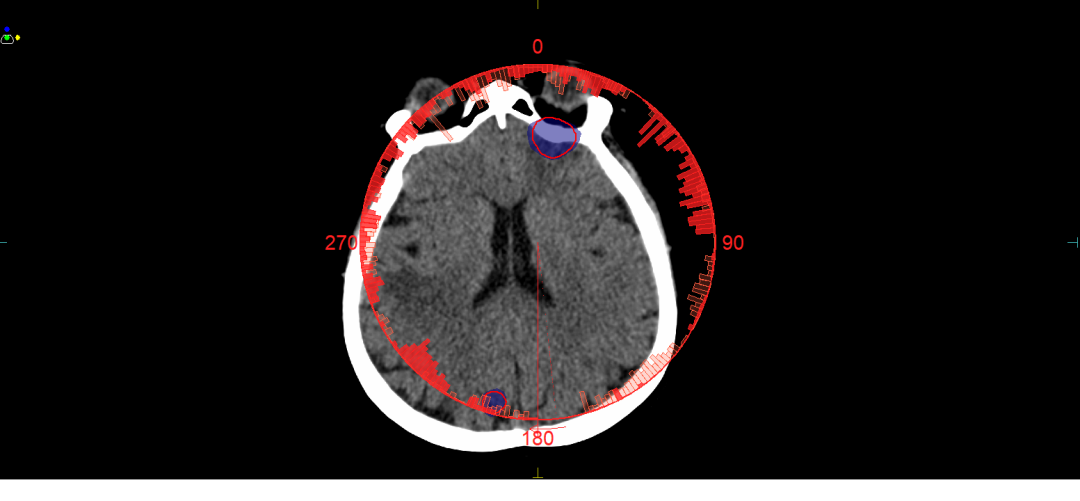

在近期治疗的案例中,一名多发性脑转移瘤患者通过分次内4D CBCT技术,实现了对微小病灶的精准打击,同时避免了对晶体、脑干的关键损伤;

图4 肿瘤位置距离晶体极近,通过治疗前的CBCT和六维床精准纠正摆位误差。